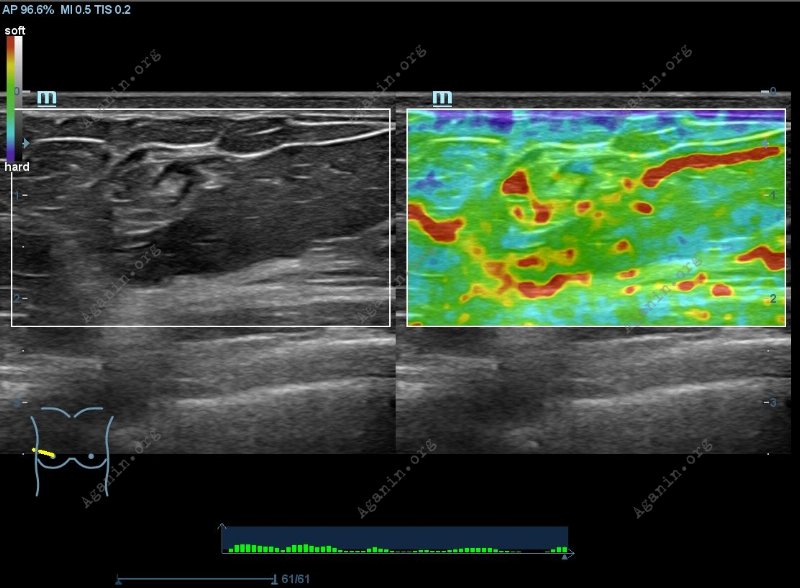

Жесткость ткани можно оценить и качественно, то есть мягче или жестче узел или образование в сравнении с окружающими здоровыми тканями.

Метод УЗИ + эластография позволяет с большой точностью выявлять злокачественность обнаруженного на УЗИ подозрительного (т.е. похожего на рак) образования какого-либо органа (например, щитовидной, молочной, поджелудочной, предстательной железы, матки и др.) Принцип выявления основан на том, что ткань злокачественной опухоли более жесткая и менее эластичная, чем здоровая.

Например, обнаружив образование молочной железы на УЗИ, можно, оценив его внешний вид, соответствующие ультразвуковые признаки и симптомы, а также жесткость образования с помощью эластографии, можно с высокой достоверностью сделать вывод о его доброкачественности или злокачественности. Таким образом, ценность УЗИ с эластографией повышается.